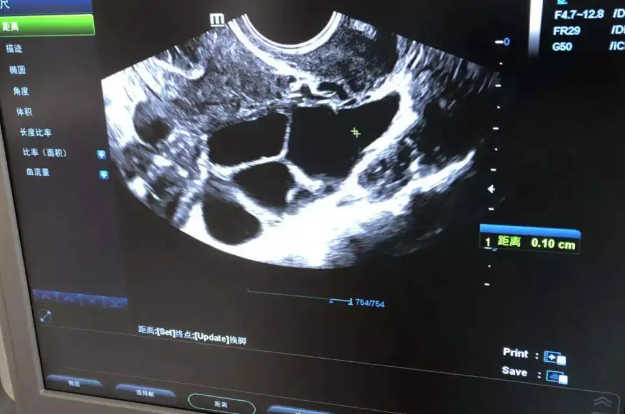

2、B超法(适用于月经不规律的妹子们)

如果你的月经周期不太规律,那就可以靠B超来帮忙啦!医生通常会在B超单上标注你的孕周结果的。如果B超单上没写孕周,没关系,你可以把孕囊大小的三个数据(单位:mm)加起来,然后除以3,再加上25,得出的数字就是你怀孕的天数啦!根据这个数字,你就可以推算出你末次月经的日期,然后再计算出你的预产期。